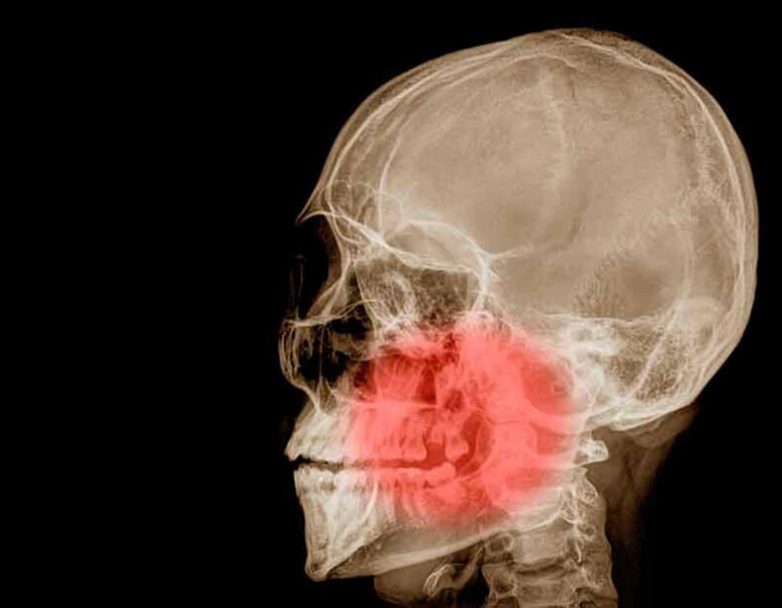

Часто люди, широко (или даже чуть-чуть) открывая рот, отмечают хруст, щелчки, болезненность в челюстном суставе, а иногда не могут полностью раскрыть рот. Почему так происходит и как восстановить функцию челюстного сустава?

Нижняя челюсть имеет суставные головки — одну справа и одну слева, которые находятся в суставных впадинах височных костей, и поэтому положение нижней челюсти напрямую зависит от положения височных костей.

Если височные кости расположены правильно, суставные впадины симметричны, то и положение нижней челюсти будет правильным. Если же височные кости смещены, то и челюсть будет волей-неволей смещаться с центрального положения.